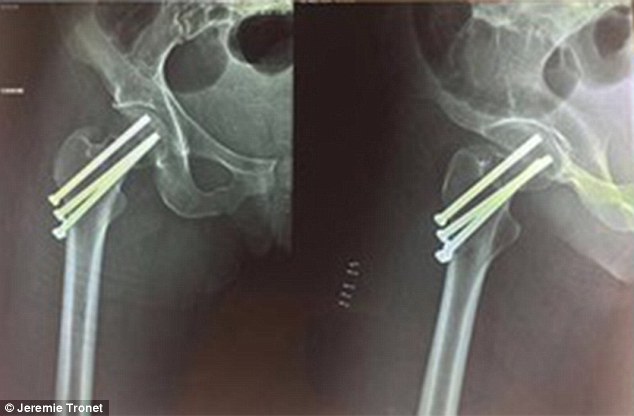

CARAIBI – Jérémie Tronet è un kite surfer di 29 anni residente ai Caraibi. Tre mesi fa, la sua ragazza ha subito un brutto incidente quando è caduta da 3 metri, fratturandosi il femore. Zoé, di 27 anni, dovrebbe affrontare 6 mesi di fisioterapia, ma non essendo coperta dall’assicurazione medica non ha diritto di accedere alle cure gratuite in un centro specializzato.